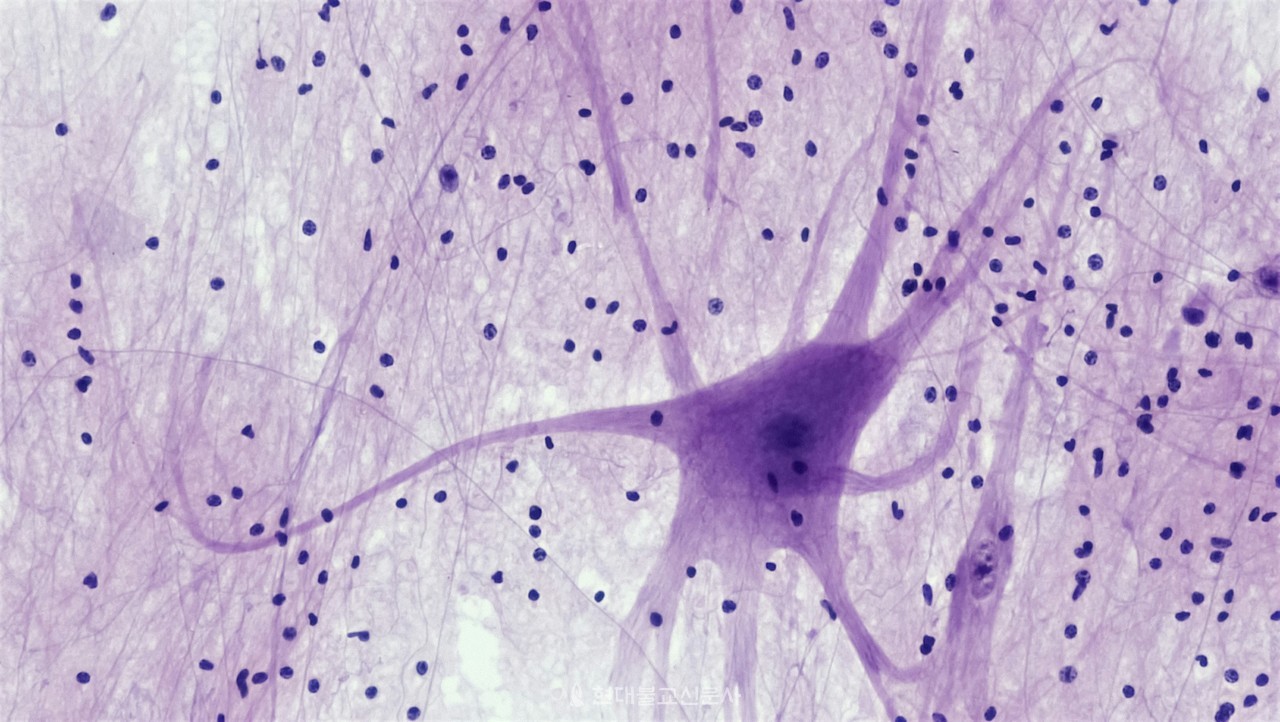

마찬가지로 의식 신경과 무의식 신경이 서로 상호 작용하면서 살아있는 시스템으로 만드는 것이 아닐까 하는 생각이 들었다. 의식 신경이 무언가를 하고자 할 때도 마음대로 자기 몸을 움직이지 못하는 것은 무의식 신경의 작용 때문인 것으로 추상할 수 있다. 생명은 입력을 알면 출력을 가늠할 수 있는 단순한 기계가 아니라는 것이다.

이런 신경은 늘 완벽하게 작동하는 것은 아니다. 신경 조직은 매우 자주 고장이 나고, 그렇게 되면 근육에 주는 운동 명령이 정확하지 않고 왜곡되거나, 명령을 내리는 속도가 느려지거나, 때로는 엉뚱한 행동을 하도록 한다. 이러한 신경 고장의 원인은 외부적인 요인 즉 수술이나 사고로 신경망이 끊어지거나, 혈관 이상으로 피의 공급량이 줄어들었을 때 자주 생긴다.

이때 무의식 신경은 근육이 빠른 속도로 반응해야 하는 자극이나 무의식적으로 반응을 일으키는 반사작용으로 근육을 움직인다. 반면에 의식 신경은 느리고 큰 힘이 들어가는 일에 작동한다. 의식 신경구조에 이상이 생겼을 때는 의학적인 진찰과 치료가 가능하지만, 무의식 신경구조에 이상이 생겼을 때는 현대 의학으로 파악하기가 어렵다.